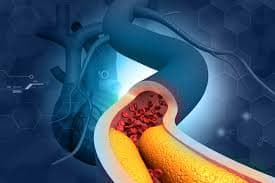

Antes de mais nada, o Tratamento para Dislipidemia controla colesterol alto, triglicerídeos elevados e outros distúrbios lipídicos que aumentam o risco cardiovascular.Além disso, acompanhamento médico contínuo […]

Antes de mais nada, Dislipidemia representa um desequilíbrio nos níveis de colesterol e triglicerídeos que compromete diretamente a saúde do coração.Além disso, essa alteração metabólica aumenta […]

Antes de mais nada, Doença Arterial Coronária representa uma das principais causas de infarto e morte cardiovascular no Brasil, exigindo diagnóstico rápido e acompanhamento especializado.Além disso, […]